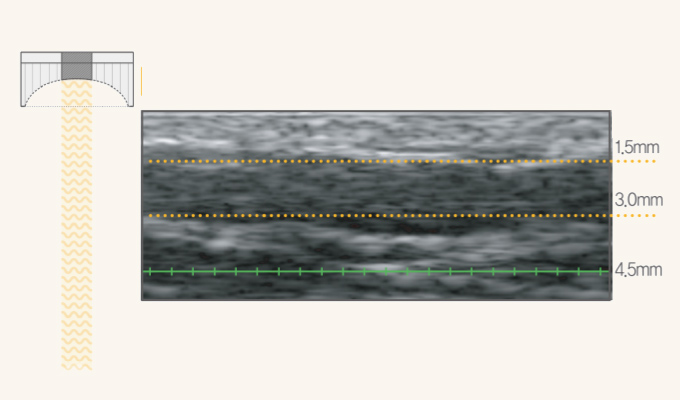

민앤정의원의 커스터마이징 차트를 통해 피부 두께와 상태를 진단하고

어떤 팁을 어느 부위에 사용할지 맞춤형 시술을 계획합니다.

개인별 피부층 확인

개인마다 피부 두께, 상태가 다르게 때문에 꼼꼼하게 확인한 후

시술 깊이, 강도, 필요한 샷 수를 계획합니다.